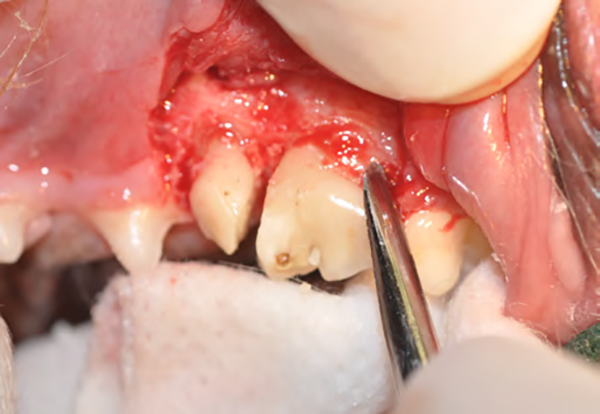

Figure 2B : Après l’élévation du lambeau, l’os alvéolaire est fraisé sur un tiers de sa hauteur (alvéolotomie) à l’aide d’une fraise boule montée sur une turbine ou un contre-angle multiplicateur, une irrigation abondante est nécessaire.

Figure 2C : Cette dent possède trois racines, elle est d’abord sectionnée en deux à l’aide d’une fraise fissure sous irrigation afin de séparer la racine distale des deux racines mésiales.

Figure 2D : Un luxateur de taille adaptée est inséré entre la racine distale et l’os alvéolaire sur toutes ses faces afin de rompre le ligament parodontal et mobiliser la racine dans son alvéole.